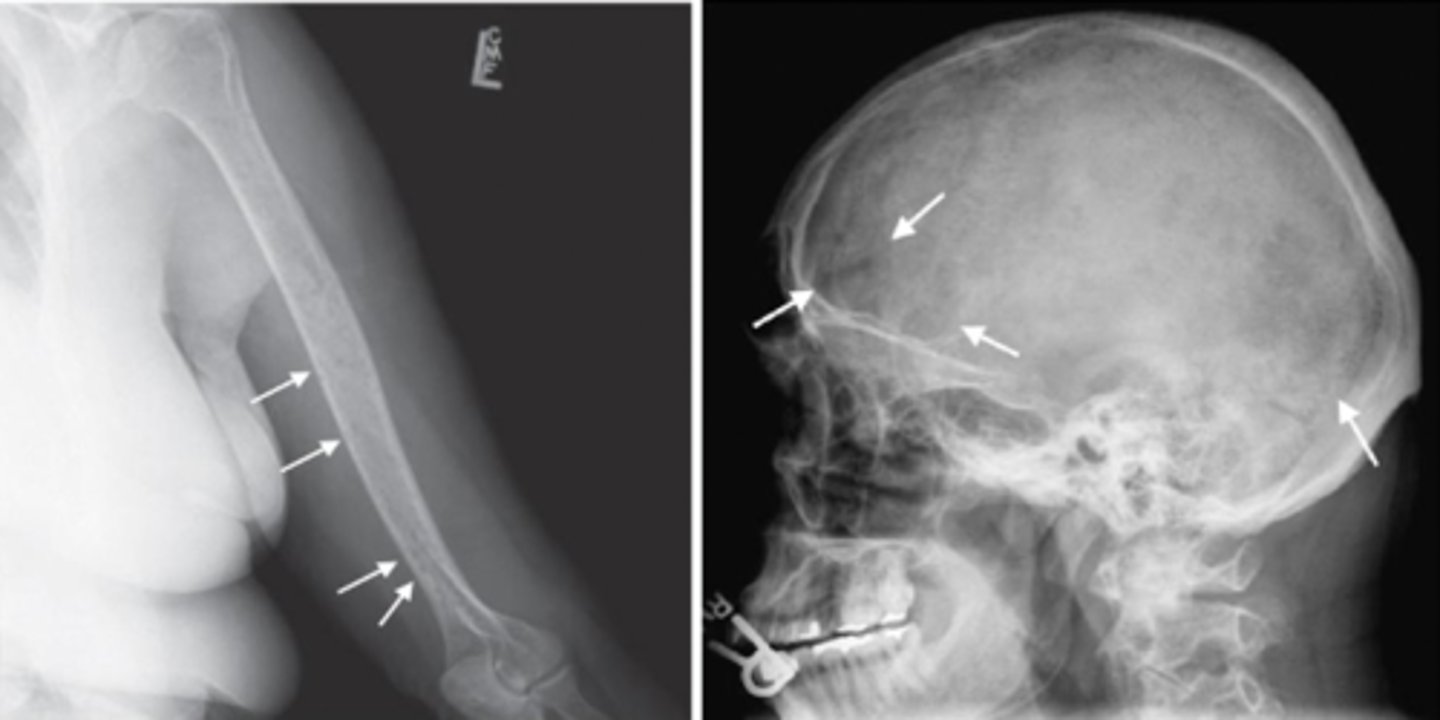

What is the pathology in this image?

Multiple myeloma

What is the pathology: cell proliferation as a result of abnormally large amount of immunoglobulin?

destructive

Is Multiple myeloma an additive or destructive (subtractive) pathology?